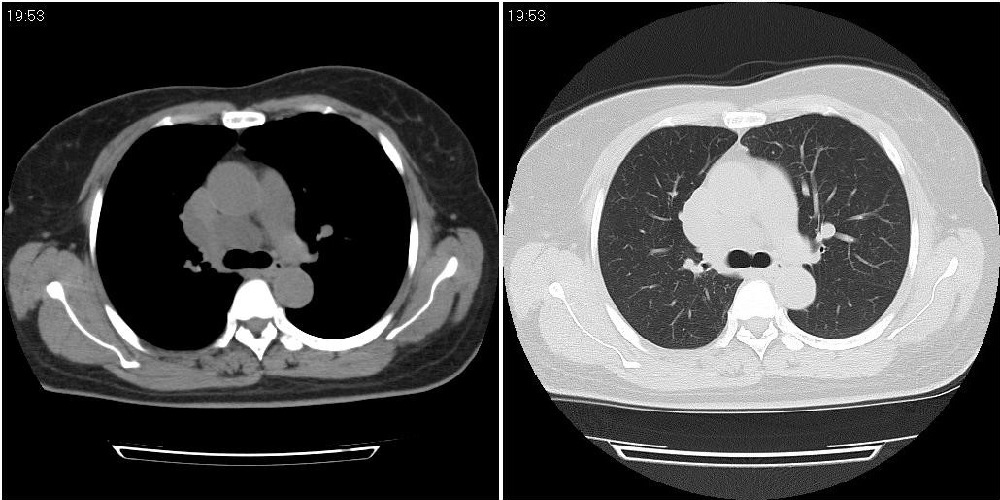

标题: CT24795:女性,47岁,右下腿静脉静脉曲张手术前体检,发现 [打印本页]

标题: CT24795:女性,47岁,右下腿静脉静脉曲张手术前体检,发现

囊性无明显占位效应:1淋巴管囊肿2畸胎瘤(其上部见小钙化)3前肠囊肿

右上纵隔囊性占位性病变;考虑淋巴管囊肿,不排除支气管囊肿。

支气管囊肿、囊性畸胎瘤、肠源性囊肿均有可能。

右上纵隔囊性占位性病变;考虑淋巴管囊肿,不排除支气管囊肿。 建议增强。

考虑淋巴管囊肿,不排除前肠囊肿。